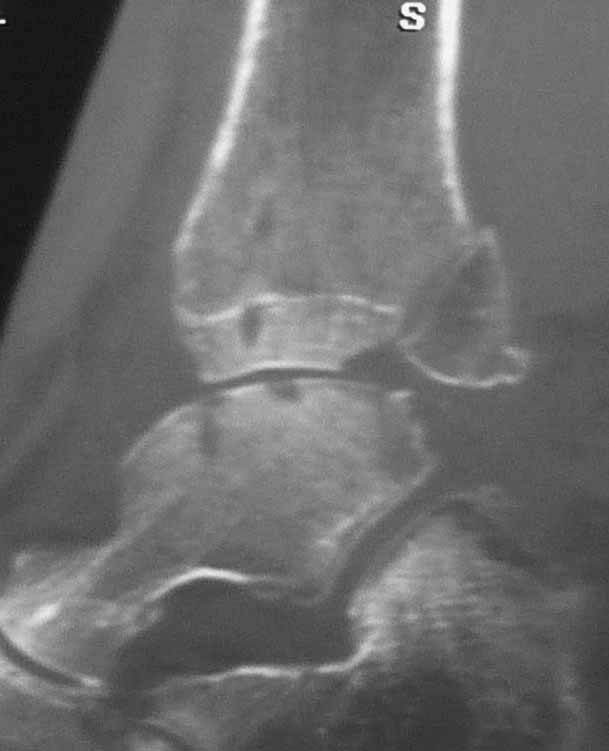

[Ortho] НА: Остаточные явления трансартикулярной фиксации голеностопного сустава при переломе лодыжек

Некорректная подача информации. Кроме утверждения, что в костях остались дырки, ценности никакой. Давайте после накостного остеосинтеза КТ делать и охать?

Какие при такой рентгенологической картине (а где рентгенограммы кстати?) имеются функциональные нарушения. И какие из них связаны с наличием дырок, но какие  с последствием перелома лодыжек? Какие жалобы предъявляет пациент при данных нарушениях функции? И, наконец, анамнез: диагностические и постоперационные рентгенограммы, послеоперационный период, реабилитация.